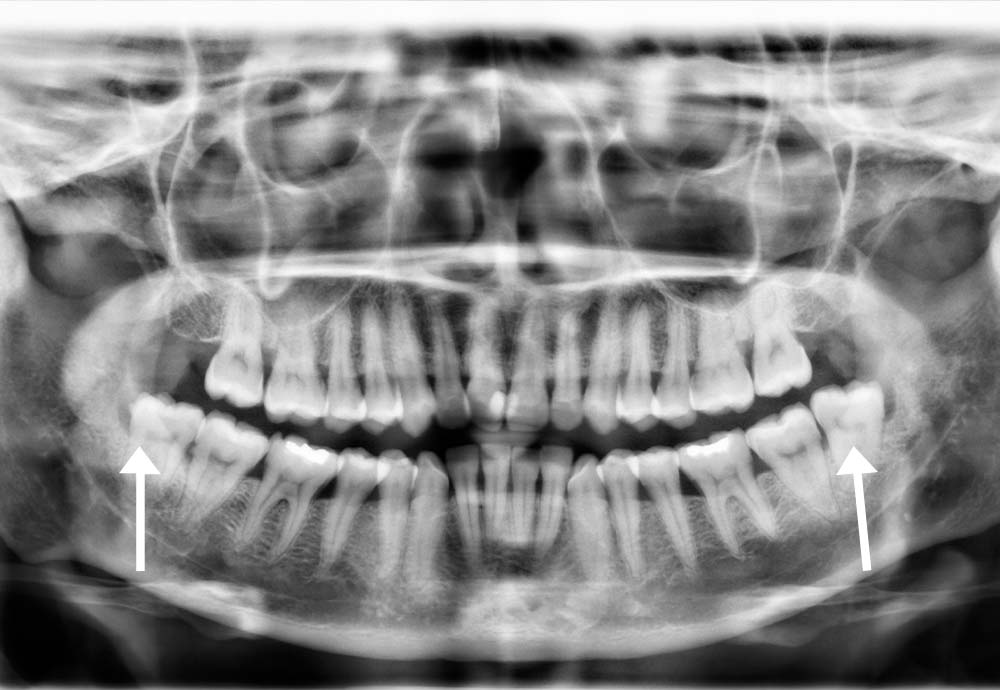

Some lower wisdom teeth can be close to the inferior alveolar nerve (which gives feeling to your lip & chin).

In rare cases, this may cause temporary symptoms such as:

These effects are usually temporary

Wisdom tooth removal is generally safe, but like any surgical procedure, there are some risks such as nerve irritation and infection.

In rare cases, lower wisdom teeth may be close to a nerve, which could cause temporary numbness. To improve safety, we use Piezo-assisted surgery and laser disinfection, which help protect nearby tissues and support faster healing.